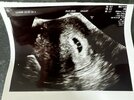

U mnie tak wyglada pęcherzyk ciążowy. Dwóch ginekologów zwróciło na to uwagę, że jest nieregularny kształt. W piątek byłam w szpitalu, byłam wtedy 6t6d i doktor zauważyła zarodek 2mm i wątpliwe tętno zarodka.

Jutro idę do gin, więc zajrzy tam i zobaczymy, ale w piątek też mam wizytę w szpitalu. Ogólnie dostałam sygnał, żebym się nie nastawiała, może być tak, że zarodek się nie rozwinie

i nastąpi poronienie. Dlatego chodzę jak na tykającej bombie.

Czytałam tu na forum, że kobiety miały takie nieregularne pecherzyki i niektóre z nich donosiły ciąże i dzieciaczki są zdrowe. A tym, którym się nie udało nastąpiło poronienie.